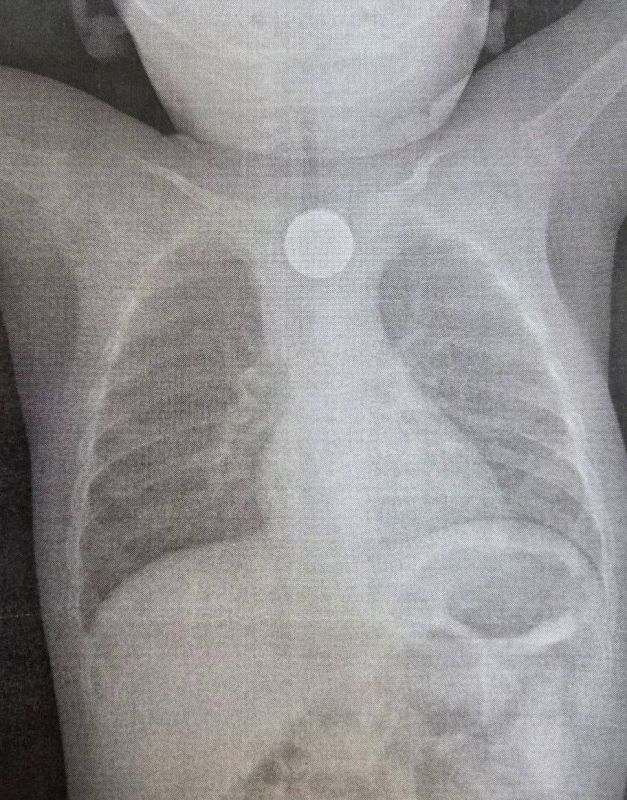

Повод для обращения шокировал даже опытных врачей: годовалый мальчик проглотил сразу два опасных предмета - монету и литиевую батарейку.Неприятности начались, когда самочувствие малыша резко ухудшилось. Сначала у него началась рвота, а...